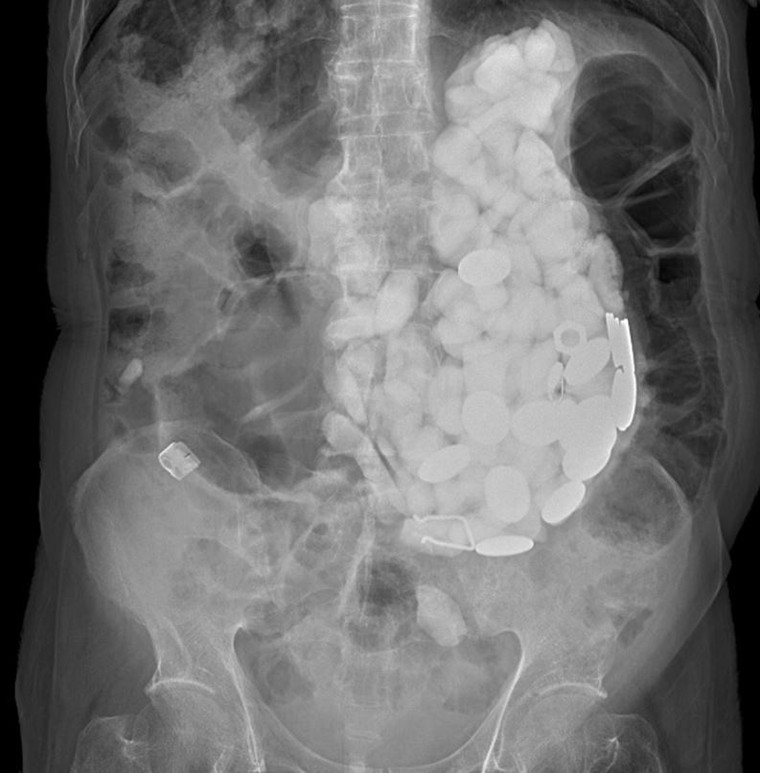

Ban đầu bác sĩ cho rằng anh bị đầy hơi, chạm vào bụng bệnh nhân bác sĩ cảm thấy vật gì đó giống như viên những hòn đá nhỏ. Sau khi chụp x-quang, bác sĩ nhận thấy có dị vật lớn, chiếm toàn bộ dạ dày của người bệnh.

Ảnh chụp X-quang cho thấy dạ dày của bệnh nhân chứa đầy vật thể lạ.

Để lấy sỏi, nắp chai và tiền xu ra khỏi bụng bệnh nhân, các bác sĩ tiến hành nội soi. Tuy nhiên, vì số lượng vật thể quá nhiều nên sau đó họ buộc phải phẫu thuật. Tổng khối lượng sỏi, nắp chai và tiền xu trong bụng của người này là 2 kg.